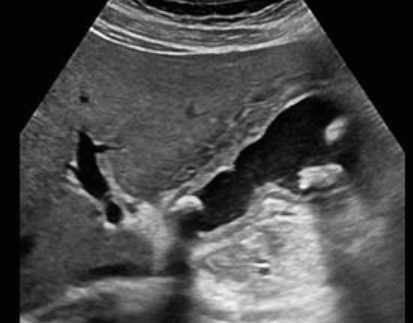

급성담낭염 US finding

- 담낭관내 결석

- 담낭벽이 두꺼워진다 ( GB wall thickness 3mm 이상)

- GB내강의 압력증가 및 확장 (width 5cm 이상)

- color doppler 시 GB wall 혈류증가 GB lumen bile sludge (내부에코증가)

- 급성담낭염은 담낭주위 액체저류 (pericholecystic fluid)

- 심한 RUQ pain (Murphy sign) : 젊은 환자에서는 대부분 Murphy sign이 있지만, 노인에서는 Murphy sign이 없더라도 급성 담낭염이 있는 경우가 많으므로 더 주의 깊게 관찰해야 한다.